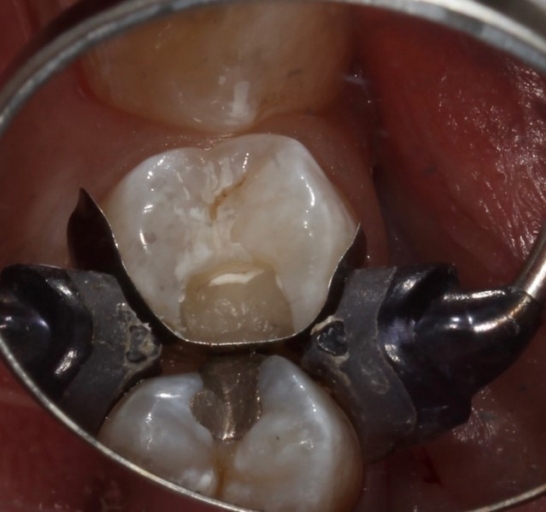

How does deep margin elevation work? Once the subgingival aspect of the prep is completed, a matrix is placed and tightly adapted to the tooth structure. A wedge is often not placed, enabling the margin elevation to reproduce an appropriate emergence profile.

The tooth is treated using the etching and bonding protocol (for composite) or a tooth conditioner (for glass ionomer or RMGI). The material can flow passively against the matrix until it is at an equigingival or supragingival location.

In some cases, the matrix band may need to be adapted to accommodate the prep’s subgingival aspect. A #2 Tofflemire band or a modified #1 Tofflemire band can extend the matrix to ensure an adequate seal of the margin elevation material to the tooth.

After adapting the matrix band so it seats further apically, it may still be challenging to have the band rest flush against the tooth. Gingival tissue may be present between the matrix band and the tooth’s subgingival margin in these instances. This increases the risk of material extending beyond the margin, leading to overhangs that are extremely difficult to correct.

To overcome this, the Belknap band can be utilized. Named after my friend and colleague, Dr. William Belknap, who taught me this technique, Teflon tape is placed between the band and the adjacent tooth.

This ensures an intimate adaptation between the band and the tooth, enabling the proper adaptation of restorative material during the margin elevation procedure. After the deep margin elevation technique is performed using the Belknap band, the Teflon tape and matrix band are removed, the new margin is refined, and the direct or indirect restoration can be completed.